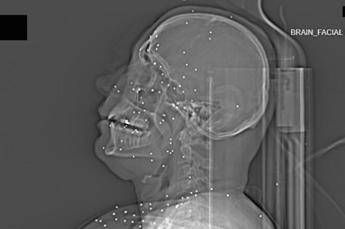

(Adnkronos) - Il Guardian, quotidiano britannico da anni impegnato nel documentare violazioni dei diritti umani, ha pubblicato un’inchiesta che aggiunge un tassello crudo e difficilmente contestabile alla comprensione della repressione delle proteste in Iran. Non si tratta di testimonianze verbali, non di racconti filtrati dalla distanza o dalla propaganda, ma di immagini mediche: radiografie e Tac. Fotografie in scala di grigi che mostrano, letteralmente, la violenza impressa nei corpi.

Il volto di Anahita – nome di fantasia, poco più che ventenne – appare come un cielo notturno attraversato da punti luminosi. Piccole sfere metalliche, da 2 a 5 millimetri, disseminate sul viso, nelle orbite oculari, persino nella massa scura del cervello. Sono proiettili “birdshot”, pallini da caccia sparati da un fucile a pompa. A distanza ravvicinata, spiegano gli esperti, non sono affatto “meno letali”: possono frantumare ossa, devastare tessuti molli, perforare facilmente un bulbo oculare. Anahita ha perso almeno un occhio, forse entrambi.

Quell’immagine non è un caso isolato. Fa parte di oltre 75 set di esami diagnostici provenienti da un singolo ospedale di una grande città iraniana, raccolti nel corso di una sola serata, durante la stretta repressiva di gennaio. Una concentrazione temporale che, già di per sé, racconta una dinamica da “mass casualty”, evento con numerose vittime simultanee, tipico degli scenari di guerra o dei grandi disastri.

Le scansioni mostrano ferite che i medici definiscono “catastrofiche”. Vahid – altro nome modificato – presenta un proiettile di grosso calibro conficcato nel collo. La trachea è spinta lateralmente, il sangue si accumula, i tessuti gonfi e danneggiati comprimono le strutture vitali. In un altro caso, un uomo di mezza età ha un proiettile sospeso nel cervello, accompagnato da una bolla di gas intracranica: segno di trauma devastante, al quale verosimilmente non si può sopravvivere. Due giovani uomini mostrano pallottole ad alto calibro alloggiate accanto alla colonna vertebrale. Una giovane donna presenta un proiettile deformato che sembra aver attraversato la gabbia toracica, lesionato il polmone e arrestato la sua corsa vicino alla spina dorsale.

Le valutazioni, condotte congiuntamente dal Guardian e dalla piattaforma di fact-checking Factnameh, sono state affidate a un panel indipendente di specialisti internazionali: medici d’urgenza, radiologi, esperti di trauma imaging e balistica. Un ex medico iraniano di pronto soccorso, anch’egli consultato, ha confermato la coerenza del software utilizzato per gli esami e l’assenza di segni di manomissione. Gli esperti precisano che, senza cartelle cliniche complete, non è possibile formulare diagnosi definitive sui singoli pazienti. Ma il quadro complessivo, spiegano, è inequivocabile.

“Se spari con armi di quel tipo contro delle persone, stai cercando di ucciderle.” La frase di uno degli specialisti di imaging traumatico riassume la sostanza tecnica dell’inchiesta. Le immagini mostrano proiettili full metal jacket, tipicamente utilizzati nei fucili d’assalto come AK-47 o KL-133, armi in dotazione ai Pasdaran, il Corpo delle guardie rivoluzionarie islamiche (IRGC). Non strumenti di controllo della folla, ma armamenti progettati per la guerra.

Accanto ai colpi di grosso calibro, emerge con forza un altro elemento: l’uso sistematico dei pallini metallici. L’Iran è tra i pochi Paesi in cui le forze di sicurezza impiegano birdshot metallico. A lunga distanza, i pallini si disperdono e colpiscono indiscriminatamente. A distanza ravvicinata, diventano devastanti: decine, talvolta centinaia di micro-proiettili che penetrano simultaneamente nei tessuti.

Le radiografie raccontano questa brutalità in modo quasi didascalico. Il torace di Ali – anche qui, nome di fantasia – contiene oltre 174 pallini metallici concentrati nella cavità destra. Il polmone parzialmente collassato, circondato da sangue e gas. Secondo gli esperti consultati, anche con un intervento chirurgico immediato e massiccio, il rischio di morte rimane altissimo.

Ma non è solo la gravità delle ferite a colpire. Caso dopo caso, le immagini mostrano corpi colpiti al volto, al torace, ai genitali. Ventinove pazienti risultano feriti al viso da birdshot. Almeno nove presentano lesioni nell’area genitale o pelvica, provocate sia da pallini sia, in alcuni casi, da fucili ad alto calibro.

Le immagini analizzate rappresentano, sottolineano gli esperti, solo una frazione del totale. In situazioni con numerosi feriti, gli ospedali sono costretti a triage severi. Le scansioni CT vengono riservate ai casi ritenuti salvabili. Molti colpiti alla testa con armi ad alto calibro, osservano i medici, “non arrivano nemmeno alla TAC”. È proprio questo aspetto a rendere l’inchiesta ancora più inquietante. Le radiografie non mostrano l’intera dimensione della violenza, ma soltanto il segmento dei sopravvissuti immediati. Coloro che, nonostante ferite devastanti, sono arrivati vivi abbastanza da essere sottoposti a esami diagnostici.

Nel loro insieme, queste immagini compongono un racconto visivo che travalica la retorica politica. Sono prove cliniche di una repressione che, secondo i medici consultati, presenta caratteristiche più vicine a un conflitto armato che a operazioni di ordine pubblico. In assenza di osservatori internazionali sul campo, la medicina diventa archivio involontario della storia. Ogni pallino visibile in una radiografia, ogni proiettile incastonato in una vertebra o in un cranio, non è soltanto un dato clinico. È la traccia materiale di una scelta: quella di usare armi da guerra contro civili, manifestanti, passanti.